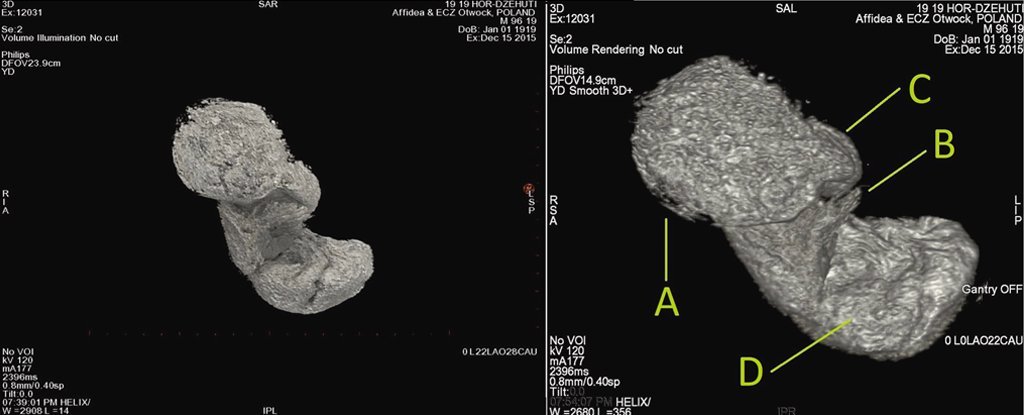

picture КТ внутрішньоутробного дослідження плода; А – голова, а Б – рукаФото: Science alert